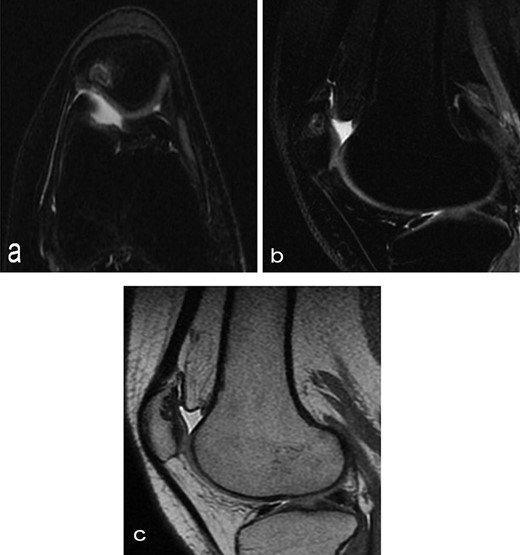

A 14-year-old female dancer presented with increasing right knee pain and functional disability without any trauma. Her pain was retropatellar pain that often radiated medially or laterally from the patella, exacerbated by climbing stairs, running and squatting. She was unable to perform any sports activities. Examination revealed peripatellar tenderness and crepitus, full range of motion and the knee was stable. Radiological examination included both MRI and computed tomography of the knee were performed at the beginning. MRI showed osteochondritis dissecans at the area at the superolateral facet of the patella in the deep subchondral area as shown in Fig. 1. This was appropriately treated conservatively with 6 months of reduced load and protected weight bearing without relief of symptoms. She quit sport activity for 2 years and then another MRI was performed Fig. 2. After 2 years we opted for adipose-derived mesenchymal stromal cells (AD-MSCs) intra-articular therapy according to the procedure described by Tremolada et al. [9]. The patient’s parents were given written information regarding the use of AD-MSCs therapy, including relative risks of this therapy and also relevant treatment alternatives that could otherwise be explored. Postoperative radiological evaluation was performed at 6 months and 12 months after AD-MSCs procedure as shown in Figs. 3 and 4. Postoperative clinical evaluation was performed using IDKC, Lysholm and Tegner scores (Table 1). After surgery, patients began a McConnell program of lateral retinacular stretching, patellar taping and vastus medialis obliquus muscle exercises. The patient was encouraged to swim and cycle to reduce impact loading. Using AD-MSC, she reported a complete relief of pain after 1 year from the procedure. Routine MRI follow-up 2 years later showed evidence of appreciable improvement in cartilage volume and osteochondral architecture at the site of injury. Early MRI T2 mapping at 6 months indicated that the area of cartilage regeneration exhibited high water content suggestive of immature cartilage or fibrocartilage morphology. Later T2 mapping at 18 months after the procedure, indicated progressive maturation of cartilage from deep to superficial layers with more hyaline like cartilage morphology. Limitations of the study are lack of arthroscopic intra-articular visualization and classification of the patella lesion.

Six months after MSC treatment in (a) axial and (b) sagital T2-weighted of MRI T2 sequences the OCD in patella showed that area of cartilage in regeneration and fill of high water content suggestive of immature cartilage or fibrocartilage morphology (c) same lesion in sagital T1 weighted MRI sequences.